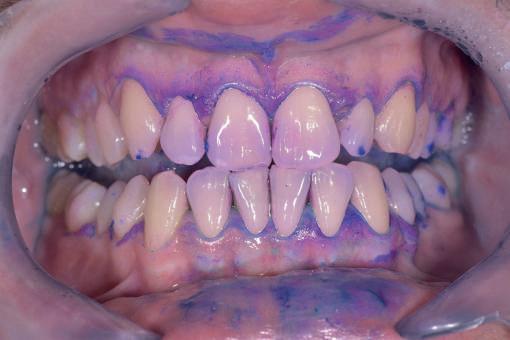

Si presenta alla nostra attenzione un paziente maschio, 35 anni, in apparente salute sistemica, fumatore, con la richiesta di controllare delle white spots, una leggera sensibilità e la richiesta di migliorare la luminosità del suo sorriso. Viene compilato e firmato il consenso informato. Il paziente viene motivato ad più efficace controllo del biofilm batterico e attraverso la condivisione dell’immagine clinica della topografia del biofilm batterico, (T.B.M.) scegliamo lo scovolino in gomma GUM Soft-picks (Sunstar) e lo sollecitiamo all’uso efficace degli spazi sovracrestali e allo spazzolamento in maniera delicata ma efficace della lingua. Sottoponiamo il paziente alla terapia parodontale non chirurgica con ablatore Comby touch (MECTRON) in modalità soft-mode per contenere la sua sensibilità. Valutiamo la sensibilità e modifichiamo i suoi stili di vita di igiene orale, di igiene alimentare e chiediamo di smettere di fumare. Il paziente riferisce di non essere disposto a rinunciare al fumo e chiediamo di ridurre il rischio di patologie e di discromie

da tabagismo passando all’uso dei dispositivi a tabacco riscaldato. Successivamente rileviamo il colore, con spettrofotometro, e con scala-colori Vita e documentiamo fotograficamente la condizione clinica presente.

Il colore rilevato è A2. Sottoponiamo il paziente ad uno sbiancamento pro-

fessionale con un principio attivo PAP (acido ftalimidoperossicaproico) che presenta il vantaggio di non sollecitare la sensibilità, pur mantenendo l’aspettativa di un risultato efficace nell’ottenere la luminosità del sorriso. Lo sbiancante ad uso professionale BRILLIANT LUMINA (Coltene), risulta essere per l’operatore di facile applicazione: ven-

gono protette le gengive con la diga liquida fotopolimerizzata, e si mescola il gel sbiancante lasciando cadere nel vasetto contenente 2 ml di gel, 3 gocce di liquido attivatore. Si ottiene il gel sbiancante di una consistenza ideale per una applicazione sulle superfici dentali sicura e pratica durante l’apposizione. Vengono eseguiti 4 step da 15 minuti.

Dopo ogni step viene aspirato il gel, pulite le superfici dentali con del cotone idrofilo e si riappone nuovamente il gel. Al termine dei 4 step, si aspira, si asciuga e viene tolta la diga. Si rileva e si condivide con il paziente il risultato ottenuto, A1, e viene documentato fotograficamente. Il paziente appare gioioso del risultato è favorevolmente colpito di non aver sofferto durante il trattamento di sensibilità. Alla persona assistita sono stati programmati dei follow-up per il trattamento successivo delle white spots con applicazioni di resine infiltranti e rigenerazione guidata dello smalto.